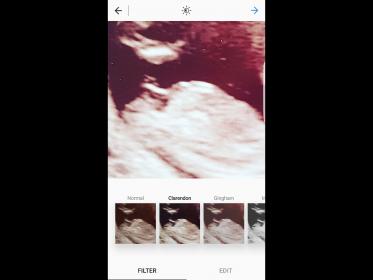

Please help me to guess the sex of my baby in this scan I've also included a zoomed in nub shot that has been lightened . I was 12 weeks and 5 days , thanks xx